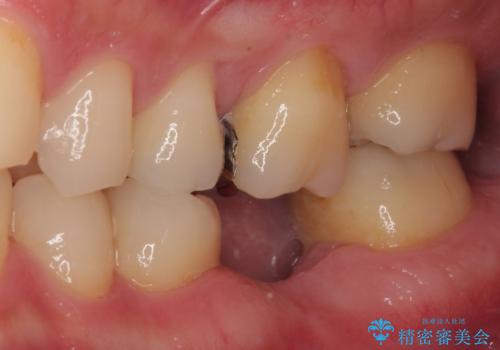

オープンバイトでかみにくい インビザラインによる矯正治療

- 前歯の上下スペースによる食べにくさを気にして来院された患者様です。

インビザラインにより上下の前歯の隙間を閉じていくこととしました。

上下の奥歯を圧下させるようにすることで、前歯を接触させるように計画しました。

上下の隙間に舌が入り込むことがオープンバイトの原因であったため、舌の筋肉のトレーニングも並行して行い、後戻りの抑制を図りました。